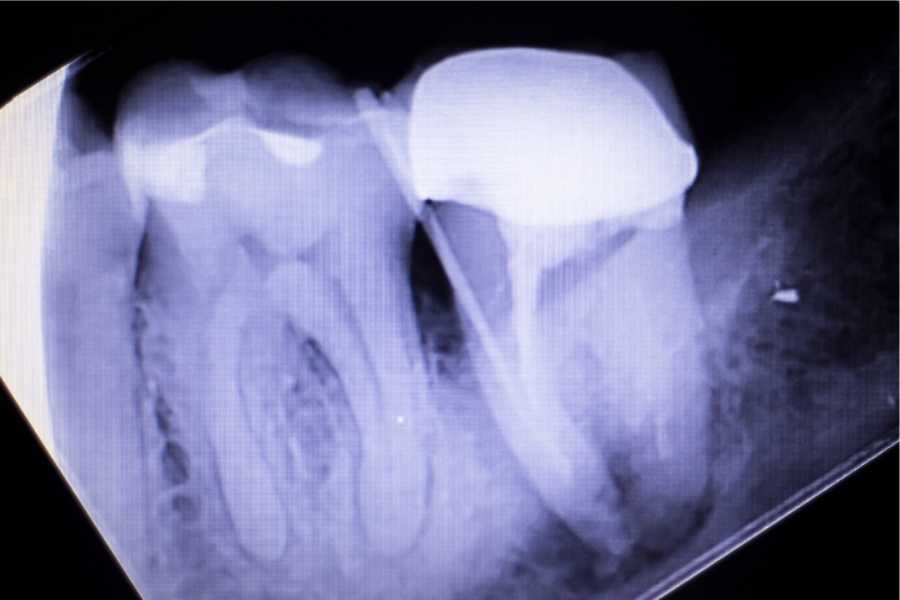

- Dişin X-ışını ile değerlendirilmesi: Diş hekimi, dişin içindeki enfeksiyonu ve hasarı belirlemek için X-ışını görüntüleri kullanır.

- Dişin temizlenmesi ve şekillendirilmesi: Dişin içindeki pulp dokusu çıkarılır, kanal temizlenir ve şekillendirilir.

- Kanalın doldurulması: Temizlenmiş kanal, biyolojik olarak uyumlu bir dolum malzemesi ile doldurulur.

- Dişin restore edilmesi: Kanal tedavisi sonrasında, dişin normal fonksiyonunu geri kazanabilmesi için bir koruyucu restorasyon uygulanır.